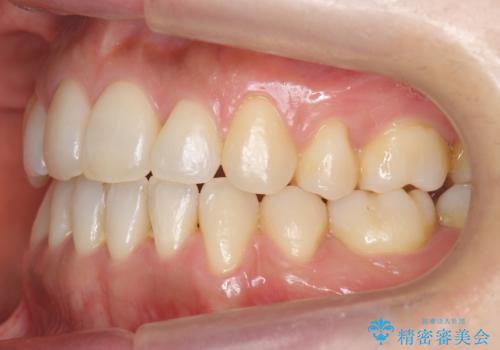

八重歯 上下の正中のずれ 40代で抜歯矯正

- 八重歯と上下の正中のずれを気にして来院。

上の前歯の正中が右にずれていました。

小臼歯抜歯を行い、ワイヤー矯正を行いました。

時間はかかりましたがしっかり治療することができました。